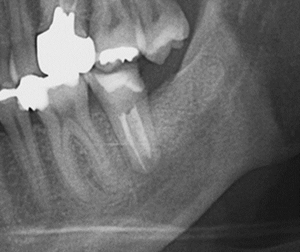

【親知らずを欠損部に移植した例】

【のう胞を伴った歯の再植例】

一度歯を抜いて、のう胞を摘出して再植しています。